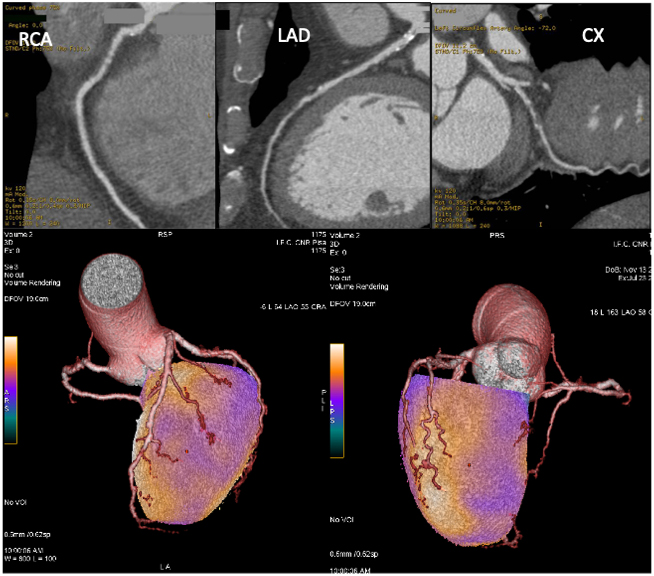

The synergistic combination of myocardial perfusion SPECT imaging with CCTA offers contrast-mediated visualization of the coronary artery lumen and detects anatomical abnormalities and their functional consequences in a single setting (Fig. 8). CCTA has an excellent negative predictive value (NPV) to exclude CAD, whereas less robust is the positive predictive value (PPV) for the identification of hemodynamically significant lesions [119, 120], since CCTA tends to overestimate stenosis severity due to coronary calcification or artifacts. CCTA can also document multivessel disease, which is viewed as a weak point of SPECT imaging due to possible balanced ischemia.

Fig. 8.Coronary CT angiography and hybrid myocardial perfusion SPECT/coronary CT angiography imaging of the patient described in Fig. 6. Upper images: CCTA showed non-calcific subcritical plaques in the right coronary artery (RCA; left side) and left anterior descendent coronary artery (LAD) and a stenotic non-calcific plaque in the left circumflex artery (CX; right side). Lower images: fusion of CCTA and SPECT datasets allows the integration of functional and anatomical data, clearly indicating the relationship between the atherosclerotic plaques and ischemic areas.